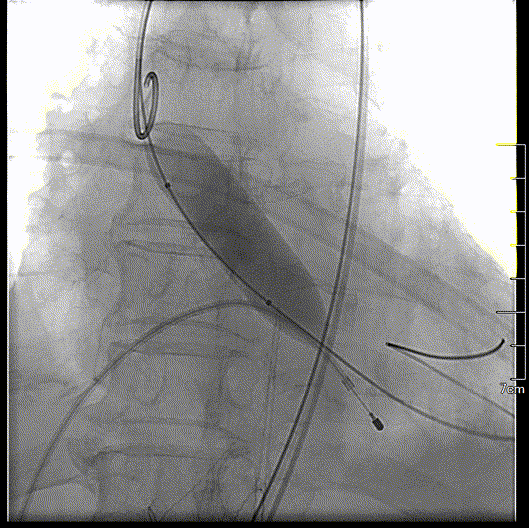

主动脉根部造影

球囊预扩,确认冠脉风险

瓣膜初始定位

瓣膜释放到可回收临界点

临界点处造影

瓣膜完全释放过程

瓣膜完全释放形态良好

工作钢丝送入左室进行起搏,180bpm起搏下预扩张主动脉瓣,完全扩张后,主动脉根部造影无反流,回撤球囊停止临时起搏。